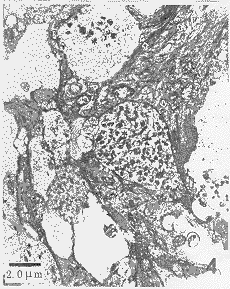

图3 猴松果体实质小叶的透射电镜图像,松果体细胞(PC)和胶质细胞(GC)。标尺示2.5 μm

Figure 3 TEM-graph of the parenchymal lobule of monkey pineak body, pinealocytes (PC) and glial cell (GC). Bar=2.5 μm

在TEM下,可见存在于结缔组织内的毛细血管,其管径约为10 μm,内皮细胞的核区向管腔凸出,内皮为带有隔膜的窗孔(50 nm)型,内皮外有明显的基膜,周围是宽阔的结缔组织间隙,可见大量胶原原纤维(图2)。松果体实质由大量松果体细胞(pinealocyte)和少数胶质细胞(glial cell)组成。松果体细胞的胞体圆形,较大,有长突起,胞质电子密度低,细胞器丰富,细胞核大,圆形和卵圆形,常带有深切迹。胶质细胞呈星状,电子密度高,细胞器较少,细胞核卵圆形或拉长(图3)。松果体细胞的长突起终止于血管周围结缔组织间隙内,突起终末呈杵状,内含200~500 nm的大型膜包密芯分泌颗粒。在松果体的结缔组织内,也可见到少数200~500 nm的膜包密芯颗粒(图4)。